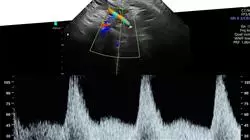

Due to the fact that this is an area in continuous development, TECH has decided to create a complete program that includes the latest information on the subject. This is the Postgraduate diploma in Prenatal Diagnosis, a dynamic, comprehensive and multidisciplinary program through which the graduates can delve into the progress of the three tests par excellence in this field: morphological ultrasound, neurosonography and fetal echocardiography. Thus, they will work for 6 months on perfecting their skills for the management of these tests, delving into the recommendations according to each case, the issues to be taken into account and the interpretation of their results.

During 6 months, the graduate will have the opportunity to delve into the advances of the three most important diagnostic tests with the Postgraduate Diploma in Prenatal Diagnosis: Morphological Ultrasound, Neurosonography and Fetal Echocardiography. In this sense, the program will help medical professionals to enhance their skills in the management of these diagnostic tests and to interpret their results effectively to offer an innovative service in the field of Prenatal Diagnosis. This Postgraduate Diploma provides 450 hours of theoretical, practical, and additional content including research articles, further reading, in-depth videos, dynamic unit summaries, and much more. In addition, this title is presented completely online, which allows specialists to connect at any time and from any device with an Internet connection. In fact, there are no face-to-face classes or specific schedules, which provides a flexible and high-level upgrade experience.